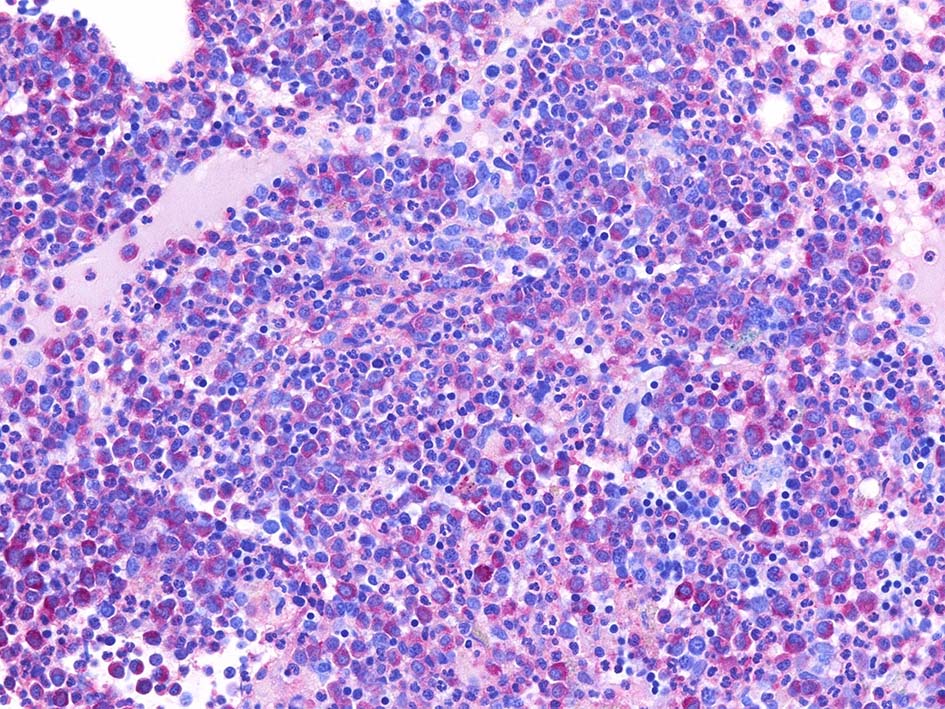

免疫染色

Fig.01: hypercellular marrow. ASDで赤染する細胞の増加=granulopoietic hyperplasiaがある.

Fig.02: 幼若な顆粒球が増加している. 赤芽球は散在しており血島は不明瞭である. 過形成髄なのにFig.02に成熟大型巨核球はみられない.

Fig.03: granulopoietic hyperplasia. 成熟顆粒球の増加もある.

ASD-Giemsa Fig.04ASD-Giemsa Fig.05CD42b染色 Fig.06

本症例ではCD34, C-KIT陽性幼若細胞が増加している. 芽球はcountで4.3%. CD34, C-KITではfocalに 5-10%.